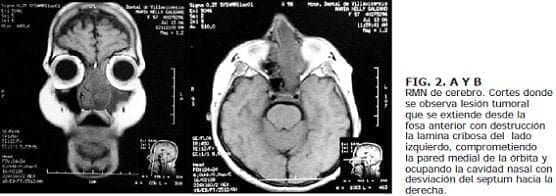

El estesioneuroblastoma no presenta un patrón definido, en los estudios de imágenes diagnósticas. Se debe sospechar al observar una lesión del tercio superior de la fosa nasal, que cause remodelación de las estructuras óseas adyacentes. Se suele observar la lesión delimitada por debajo de la lamina cribiforme. En la tomografía se observa un tumor negro intenso y brillante que causa remodelación ósea adyacente. La resonancia muestra una lesión hiperintensa en el T2. e isointensa en el T1 . que es invasora. La resonancia magnética es el estudio de elección para definir y valorar la extensión intracraneana (16).